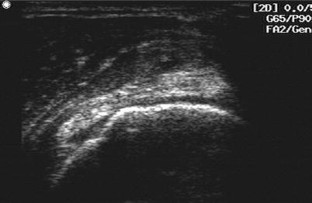

Bildgebende Verfahren bei Rotatorenmanschettendefekten der Schulter

Imaging in evaluating rotator cuff tears

Vor der Indikation zur bildgebenden Diagnostik steht die klinisch begründete Verdachtsdiagnose. Die Basis der bildgebenden Diagnostik bei Rotatorenmanschettendefekten bilden die konventionelle Röntgendiagnostik und die Sonographie. Für spezielle Fragestellungen bietet sich die Kernspintomographie an. Sehnentotaldefekte können sowohl im MRT als auch mit der Sonographie mit großer Sicherheit erkannt werden. Die Diagnostik von Partialdefekten der Manschette ist weiterhin verbesserungswürdig. Die Sicherheit des nativen MRT in der Diagnostik von Partialdefekten kann sowohl durch die indirekte als auch die direkte MR-Arthrographie deutlich gesteigert werden. Nur die Sonographie bietet bislang die Möglichkeit, im Echtzeitverfahren am bewegten Gelenk zu untersuchen. Mit der dynamischen Muskelsonographie sind zusätzliche Möglichkeiten gegeben, die Funktionsfähigkeit der Muskulatur zu erfassen. Der Einsatz der MRT als Screeningmethode sollte unterbleiben, da mit ihrer Hilfe keine therapeutisch relevanten Informationen gewonnen werden.

Diagnostic imaging in a patient with shoulder pain should be used only after a comprehensive clinical evaluation of the shoulder. X-ray and ultrasonography are the basic diagnostic tools; computed tomography and magnetic resonance imaging (MRI) should be used only with certain indications. Ultrasonography and MRI have comparable accuracy for identifying and measuring full-thickness rotator cuff tears, but the accuracy for identifying partial-thickness still needs to be improved. MR arthrography has significantly improved sensitivity and specificity for partial-thickness tears of the cuff. Only ultrasound provides a real-time examination tool during shoulder movements. Moreover, dynamic ultrasonography can assess the contraction patterns of the supraspinatus and infraspinatus muscles, which may improve decision making in the treatment of shoulder diseases. In depicting fatty atrophy of the supraspinatus and infraspinatus muscles, MRI remains the reference standard. MRI should not be used as a diagnostic screening tool in patients with chronic shoulder pain because it does not appear to significantly affect treatment or outcome.